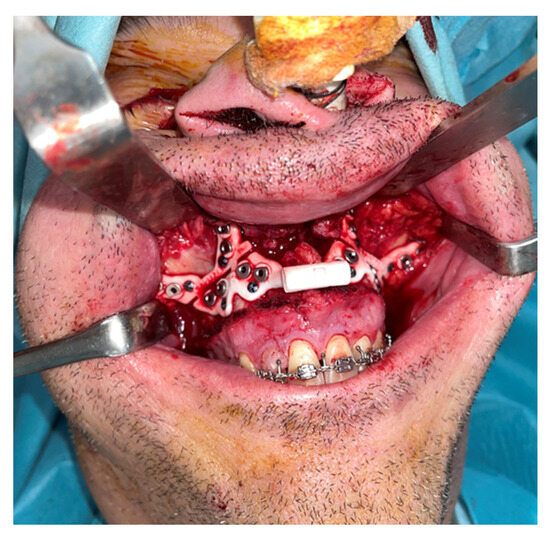

An intraoral incision was designed in the upper vestibule, above the dental apices, extending from the right first molar to the left first molar. The mucoperiosteal flap was elevated to expose the maxilla. The bone-supported cutting guide was then positioned on the maxilla. Two cutting guides were designed, joined at the medial part, each with a tab for positioning on the piriform process. The cutting guide was designed to be fixed with 2.0 mm screws (Figure 3).

A Le Fort-type osteotomy was performed using a reciprocating saw. The maxilla was positioned according to the preoperative planning and fixed with customized titanium plates (Figure 4). The intermediate splint was used to perform a double check of the patient’s correct position of the maxilla and the dental occlusion.

Figure 3. Step 3. Intraoral approach via vestibular sulcus incision and positioning of the maxillary bone-supported cutting guide, corresponding to the first surgical step following VSP.

Figure 4. Le Fort I osteotomy and fixation of the maxilla using customized plates, verifying transfer of the virtual plan to the surgical site.